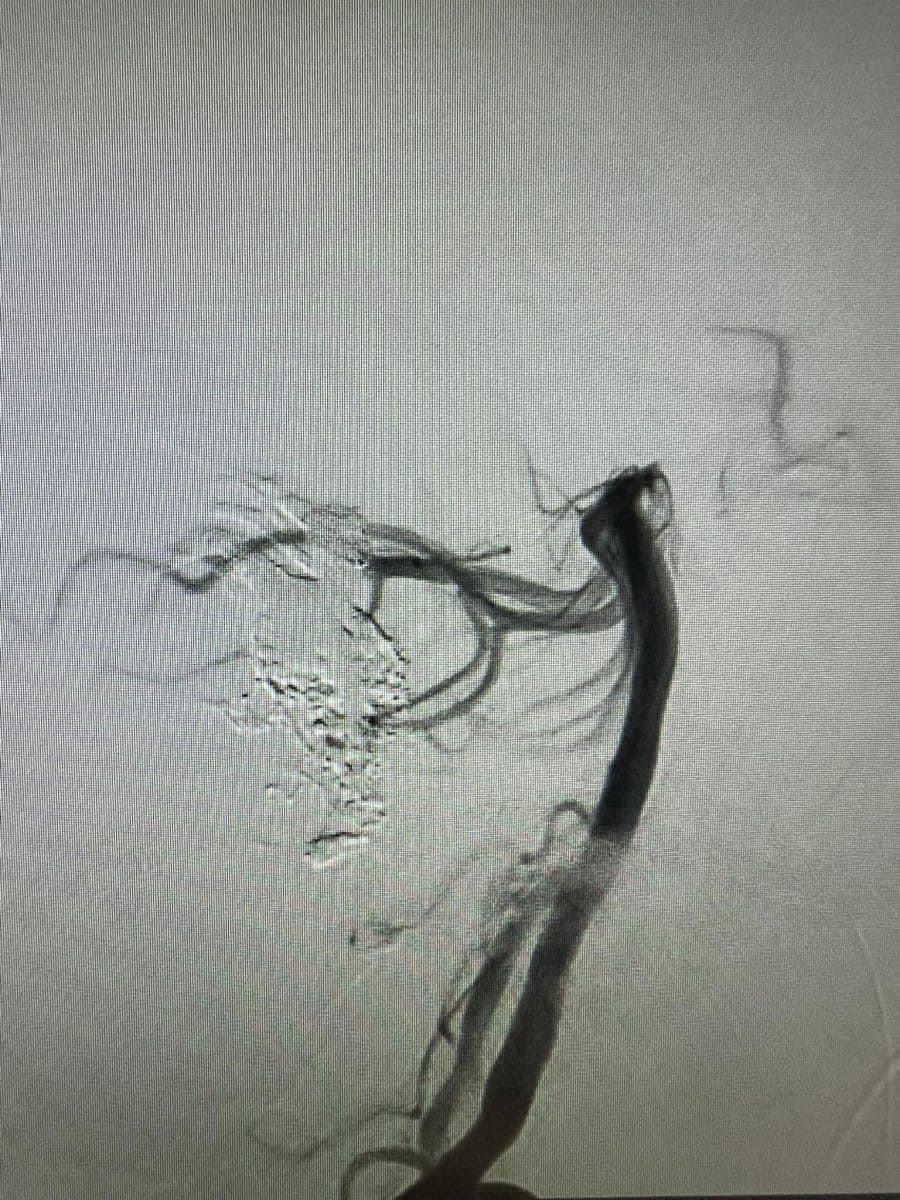

Δια ζώσης συμμετοχή των φοιτητών του Πανεπιστημίου Πατρών σε εξειδικευμένες τεχνικές ενδοαγγειακής αντιμετώπισης αγγειακών δυσπλασιών του κεντρικού νευρικού συστήματος.

Στην επέμβαση συμμετείχαν ο Καθηγητής Ενδοαγγειακής Νευροχειρουργικής Κος Β. Παναγιωτόπουλος, ο Καθηγητής Επεμβατικής Νευροακτινολογίας κος Π. Ζαμπάκης, ο επιμελητής επεμβατικής ακτινολογίας κος Μ. Θεοφάνης και ο αναισθησιολόγος κ. Γούδας.